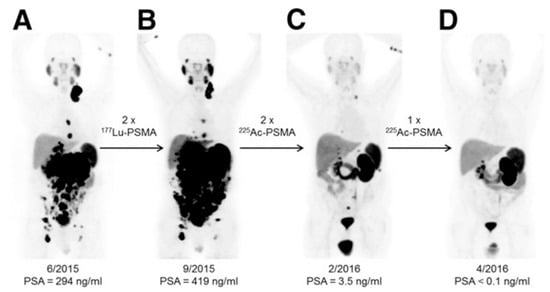

- Kratochwil, C.; Bruchertseifer, F.; Giesel, F.L.; Weis, M.; Verburg, F.A.; Mottaghy, F.; Kopka, K.; Apostolidis, C.; Haberkorn, U.; Morgenstern, A. 225Ac-PSMA-617 for PSMA-targeted α-radiation therapy of metastatic castration-resistant prostate cancer. J. Nucl. Med. 2016, 57, 1941–1944. [Google Scholar] [CrossRef]

- Kratochwil, C.; Haberkorn, U.; Giesel, F.L. 225Ac-PSMA-617 for Therapy of Prostate Cancer. Semin. Nucl. Med. 2020, 50, 133–140. [Google Scholar] [CrossRef]

- Sathekge, M.; Bruchertseifer, F.; Knoesen, O.; Reyneke, F.; Lawal, I.; Lengana, T.; Davis, C.; Mahapane, J.; Corbett, C.; Vorster, M. 225Ac-PSMA-617 in chemotherapy-naive patients with advanced prostate cancer: A pilot study. Eur. J. Nucl. Med. Mol. Imaging. 2019, 46, 129–138. [Google Scholar] [CrossRef]